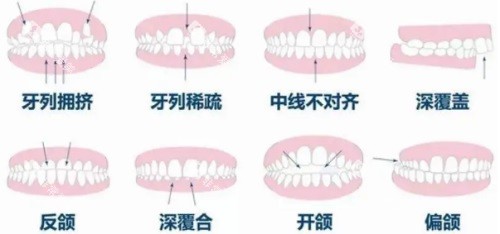

金属托槽矫正:10000-15000元

陶瓷托槽矫正:15000-20000元

隐形矫正(国产):20000-30000元

隐形矫正(进口):30000-50000元

保持器:500-1000元

儿童正畸:5000-15000元